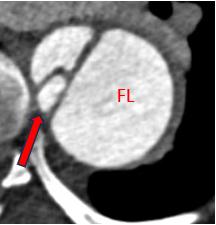

Background: Aortic dissection is the second most common reason for aneurysmal degeneration. While endovascular repair is preferred over open techniques, this approach remains challenging, and multiple secondary interventions are required for complications related to dissection of potential landing zones (LZs) (Fig 1). This study aims to report the early outcomes of routine adjunctive use of transcatheter electrosurgical septotomy (TES) to optimize LZs for endovascular repair of post-dissection aortic aneurysms (PDAAs).

Methods: Consecutive endovascular repairs with adjunctive TES performed for PDAAs between 2022-2023 at two institutions were reviewed. TES was systematically performed to ensure that all grafts were deployed within false lumen-free LZs (Fig 2). Endpoints included TES technical success, defined by the absence of any type Ia or Ib endoleak or entry flow, procedure technical success, aortic true lumen (TL) diameter expansion, major adverse events (MAEs), and 30-day mortality.